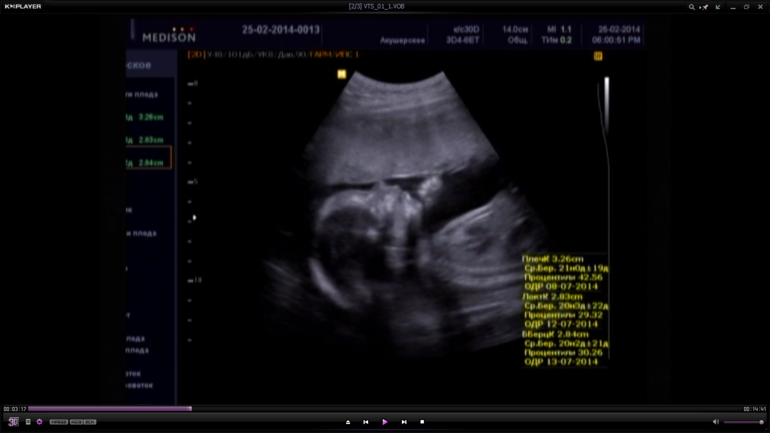

Второй скрининг я уже делала в этом же центре в 20-21 нед, на котором у нас славу богу все было хорошо, девочку нам подтвердили, сказали примерный вес 362 гр.

Ну и последний скрининг в 32 недели, наш вес 2058 гр. Мы уже заметно подросли что не помещались на экран))) Доча упорно закрывалась ручками и не захотела показывать свое лицо, в итоге ни одной нормальной фотки так и не получилось(((